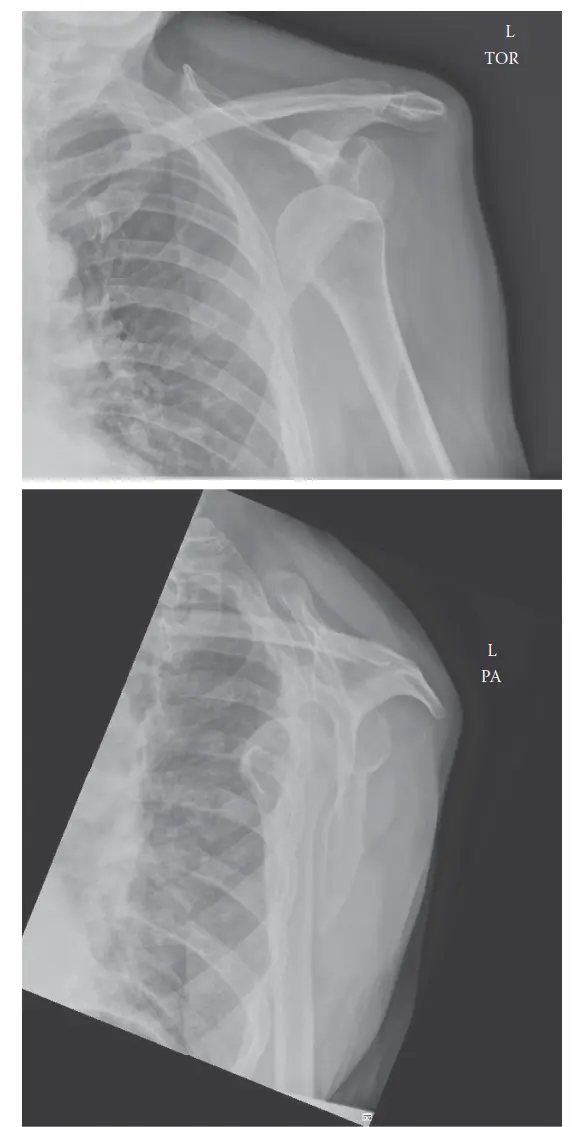

التشخيص الدقيق لخلع الكتف الأمامي

يُعد التشخيص الدقيق والسريع لخلع الكتف الأمامي أمرًا بالغ الأهمية لضمان العلاج الفوري والفعال وتحديد أي إصابات مصاحبة. يعتمد الأستاذ الدكتور محمد هطيف على نهج شامل يتضمن التاريخ المرضي، الفحص السريري، والتصوير الطبي المتقدم.